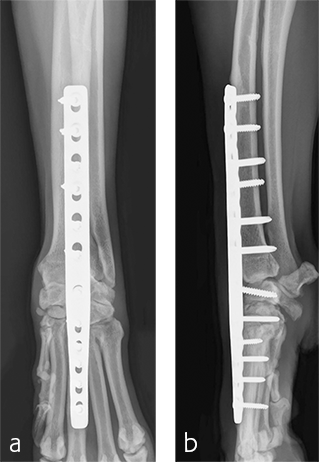

A 2.7/3.5 Pancarpal Arthrodesis was applied to the dorsal aspect of the carpus using a combination of locking and cortical screws. A 2.7 mm cortical screw was used to attach the plate to the radiocarpal bone. Five 2.7 mm locking screws were used to attach the plate to the 3rd metacarpal bone. Five 3.5 mm locking screws and one 3.5 mm cortical screw were used to attach the plate to the dorsal surface of the radius. A combination of locking and cortical screws was used to provide compression (cortical screw placed in eccentric position to provide compression across the radiocarpal joint) and achieve excellent stability and limb alignment. The incision was closed in routine fashion.

Postoperative radiographs revealed proper joint orientation and compression of the multiple antebrachiocarpal joint levels (Fig 5). Implant placement was considered excellent.